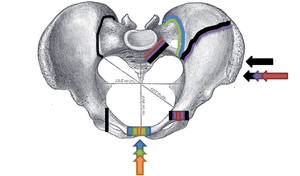

Fractures of the superior (in two places) and inferior pubic rami on the person's right, in a person who has had prior hip replacements

Pelvic fractures are most commonly described using one of two classification systems. The different forces on the pelvis result in different fractures. Sometimes they are determined based on stability or instability.[2]